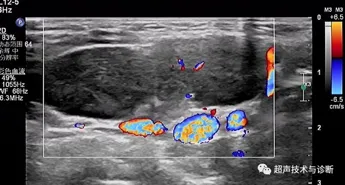

超声作为评估淋巴结最便捷、最直观的检查,能够快速评估淋巴结的形态、结构和血流特征。

淋巴结作为外周免疫系统的核心,由皮质、髓质和包膜3部分组成,广泛分布于颈部、腋窝、腹股沟等淋巴回流区域。根据解剖位置,可分为易触及的浅表淋巴结和难触及的深部淋巴结。儿童淋巴结大小的评估应综合年龄、解剖部位等进行个体化判断。当颈部淋巴结长径>20mm或短径>10mm时;腋窝淋巴结短径>8mm;滑车上淋巴结>5mm;肠系膜区域淋巴结长径>15mm或短径≥8mm或同一超声切面显示有3个或更多聚集时,即可诊断。